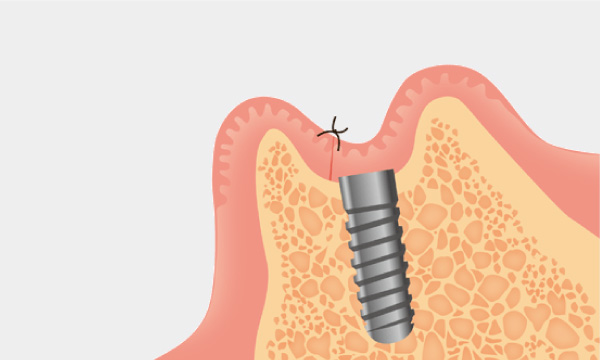

インプラント治療とは術前診査・診断を十分に行った上で、歯が抜けてしまった部分にインプラント(人工歯根)を埋め込み、その上から自然な見た目の人工歯を装着させるという治療法で、骨にしっかりとインプラント(人工歯)を定着させるため、自分の歯のようにしっかり、思い切り噛めるようになります。